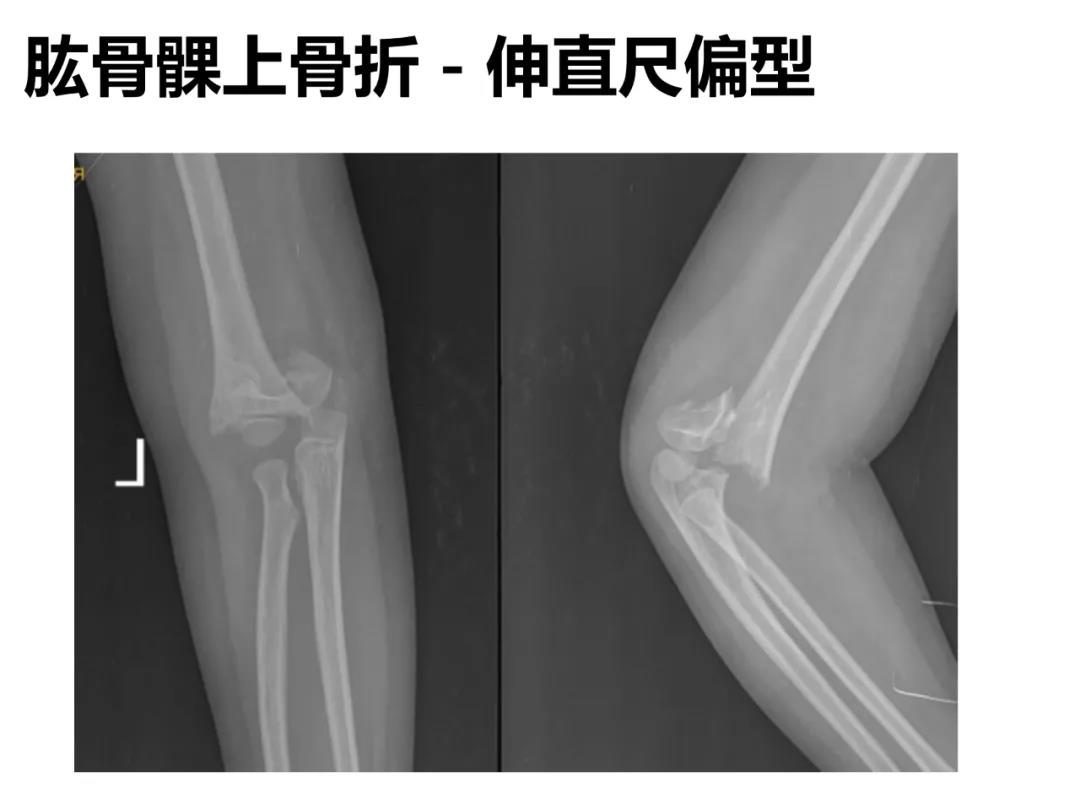

小儿骨科X线片汇总,临床读片宝典!